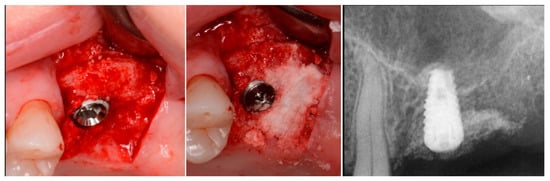

Figure 5.

Implant placement into the crestally elevated sinus site (left), additional EthOss graft material to fill a crestal concavity (middle) and a radiograph following implant placement and flap closure (right).

The patient returned at 10 weeks to initiate the restoration of the integrated implant. The implant was exposed, and the cover screw was removed (Figure 6, left). An impression was obtained, and a healing abutment was placed on the site while the restoration was fabricated at the laboratory. Following return of the restoration from the lab, the patient presented. The healing abutment was removed, and a screw-retained restoration was inserted and the screw torque was adjusted to the manufacturer’s recommendation (Figure 6, middle). A periapical radiograph was obtained to verify the seating of the restoration and graft incorporation with the surrounding host bone (Figure 6, right).

Figure 6.

Exposure of the integrated implant after 10 weeks of healing (left). Screw-retained restoration placement (middle) and a radiograph to document seating of the restoration at the implant connector demonstrating conversion of the graft material to host bone (right).